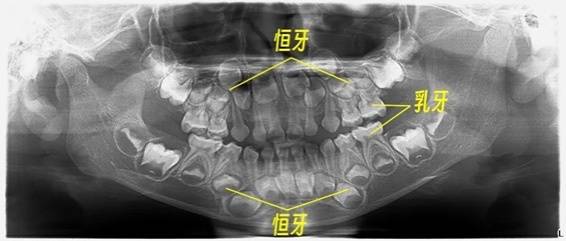

你以为婴儿是在出生后6个月左右才长牙?错了。实际上,怀孕2个月左右,婴儿的牙齿发育钙化就开始了。

在出生前,20颗乳牙已基本形成,只是还未萌出;直到出生6个月之后,才依次萌出。恒牙也不是6岁后才开始生长的,而是从胚胎第4-5个月时,牙胚就开始发育了。

而且,孕期如果患口腔疾病,可能影响维生素A、C、D和钙、磷等矿物质吸收,影响胎儿牙胚的正常形成和钙化, 从而影响到孩子出生后牙齿的健康和全身发育。